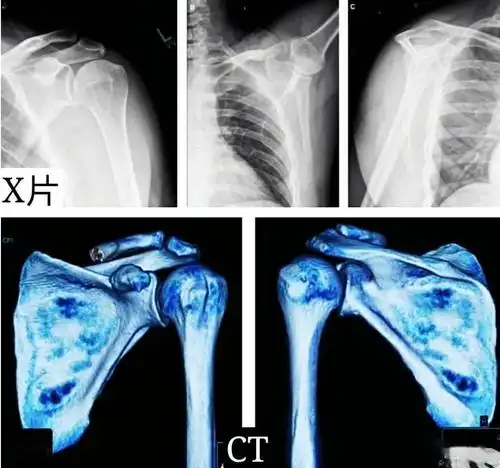

请问一下肩胛骨正侧位怎么摆位和影像显示谢谢